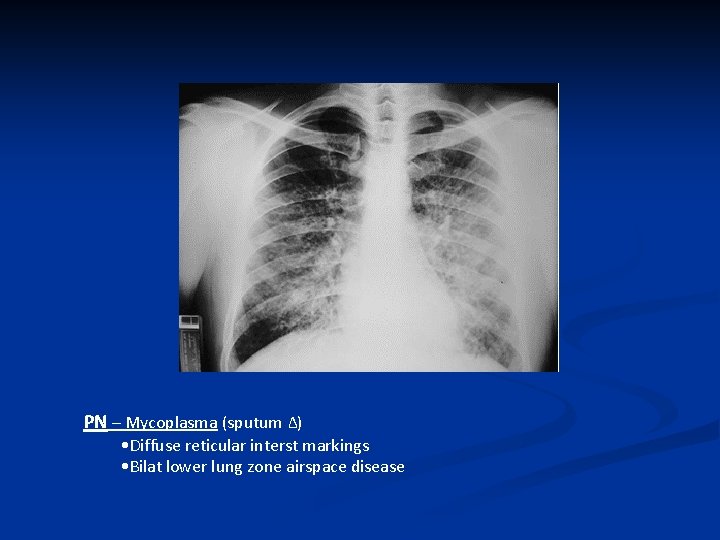

Recognizing Airspace Dz 2012